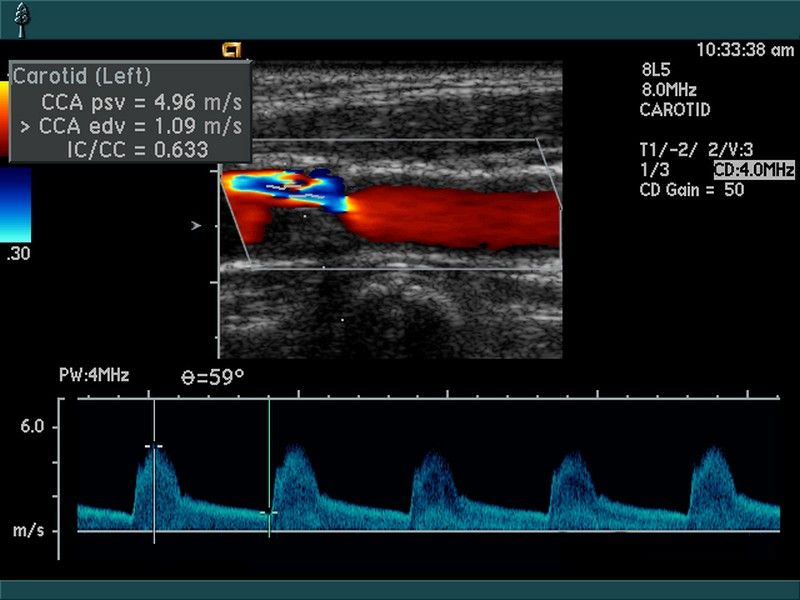

Когда проводится дуплексное УЗИ вен, аппарат используют одновременно в двух режимах: обычном и допплеровском. Первый вариант считается традиционным. Это режим ультразвукового сканирования, который позволяет увидеть вену в двухмерном изображении. Таким образом можно увидеть аномалии развития, а также ее строение. Благодаря допплеровскому режиму удается оценить текучесть крови, направление ее движения, скорость кровотока. Эта информация также полезна для врача, так как помогает поставить точный диагноз и назначить правильное лечение.